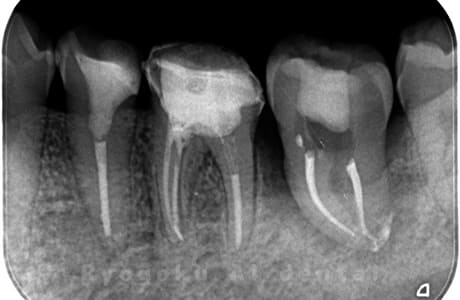

Case04

-

- 原因

- 慢性根尖性歯周炎

- 治療内容

- 自家歯牙移植

- 治療費用

- 220,000円

他院で抜歯し、インプラントを進められた患者さんです。親知らずが残っていたため、移植治療がベストと判断し、治療を行いました。

<リスク・副作用>

治療後、痛みや違和感、出血、腫れなどが出る事があります。喫煙者、糖尿病などの方の場合、歯が生着しない場合があります。